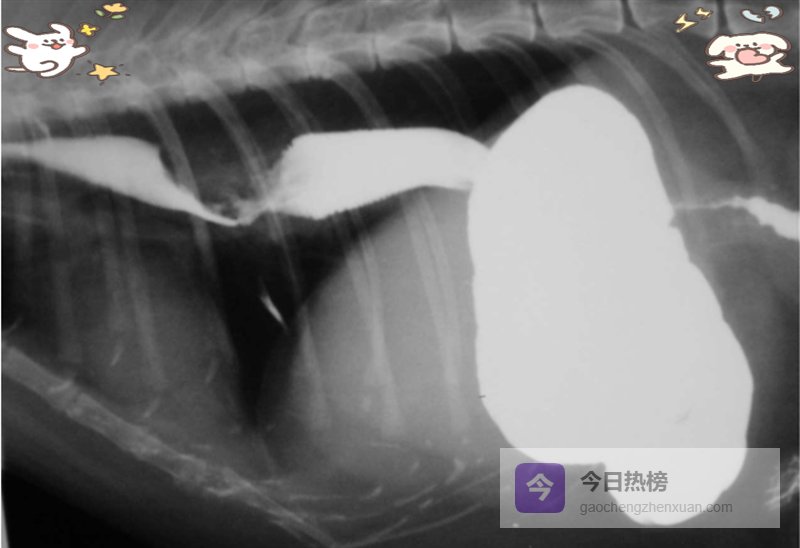

5.2 【 X光:先排除“其他元凶” 】胸片常规无异常,但别忽略巨食道症、血管环、异物、肿瘤或疝气(图2)。上消化道钡餐能动态观察胃食管反流、钡剂滞留、节段性扩张(图3),但正常猫狗也会偶见GER,因此必须结合临床症状与内镜病理综合判断。

图3. 钡剂食道造影显示猫食道肿物